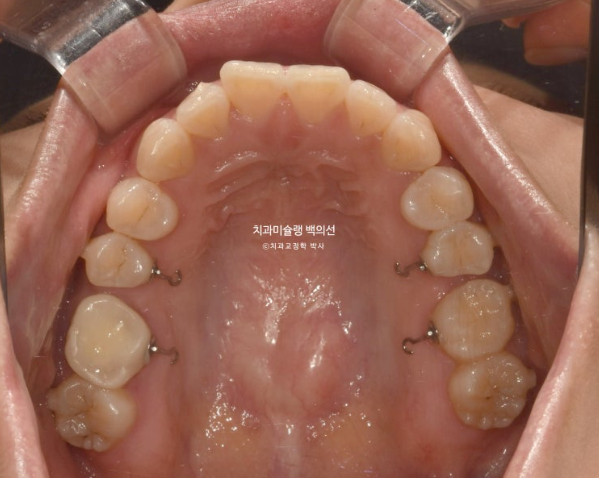

25년 5월부터 8월까지 14개 추가장치를 모두 낀 후 치료를 마무리 했습니다.

25.08

이제 전후비교 보겠습니다.

총 치료기간은 1년 10개월, 재제작은 2회 했습니다.

23.10~25.08

발치된 큰어금니 자리를 뒤에있는 제2대구치와 사랑니로 감쪽같이 대체되었습니다.